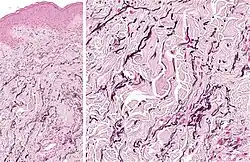

Thick elastic fibers consisting of bundles of elastin in the human lung

Elastin serves an important function in arteries as a medium for pressure wave propagation to help blood flow and is particularly abundant in large elastic blood vessels such as the aorta. Elastin is also very important in the lungs, elastic ligaments, elastic cartilage, the skin, and the bladder. It is present in jawed vertebrates.[17]